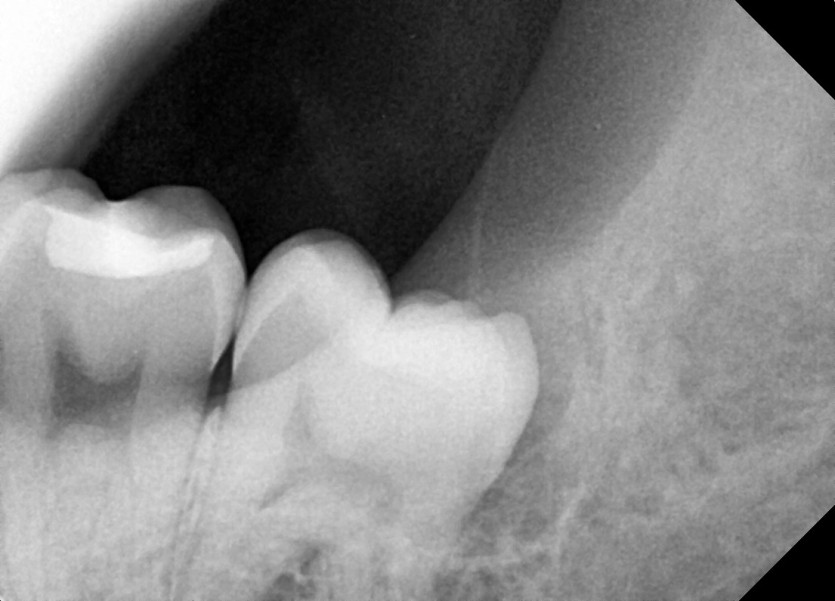

#38 사랑니 발치

구강 외과 전문의가 당일 발치했습니다.